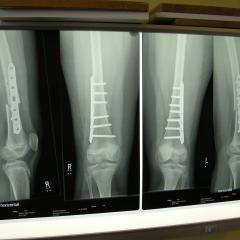

XRays